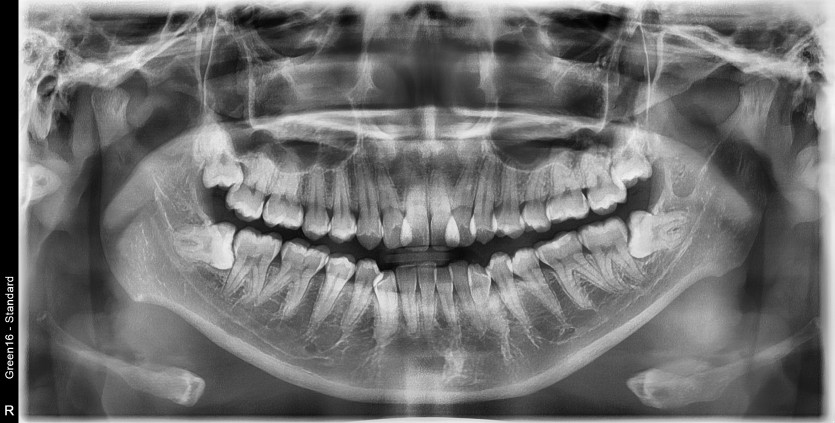

#38 사랑니 발치

구강 외과 전문의가 당일 발치했습니다.